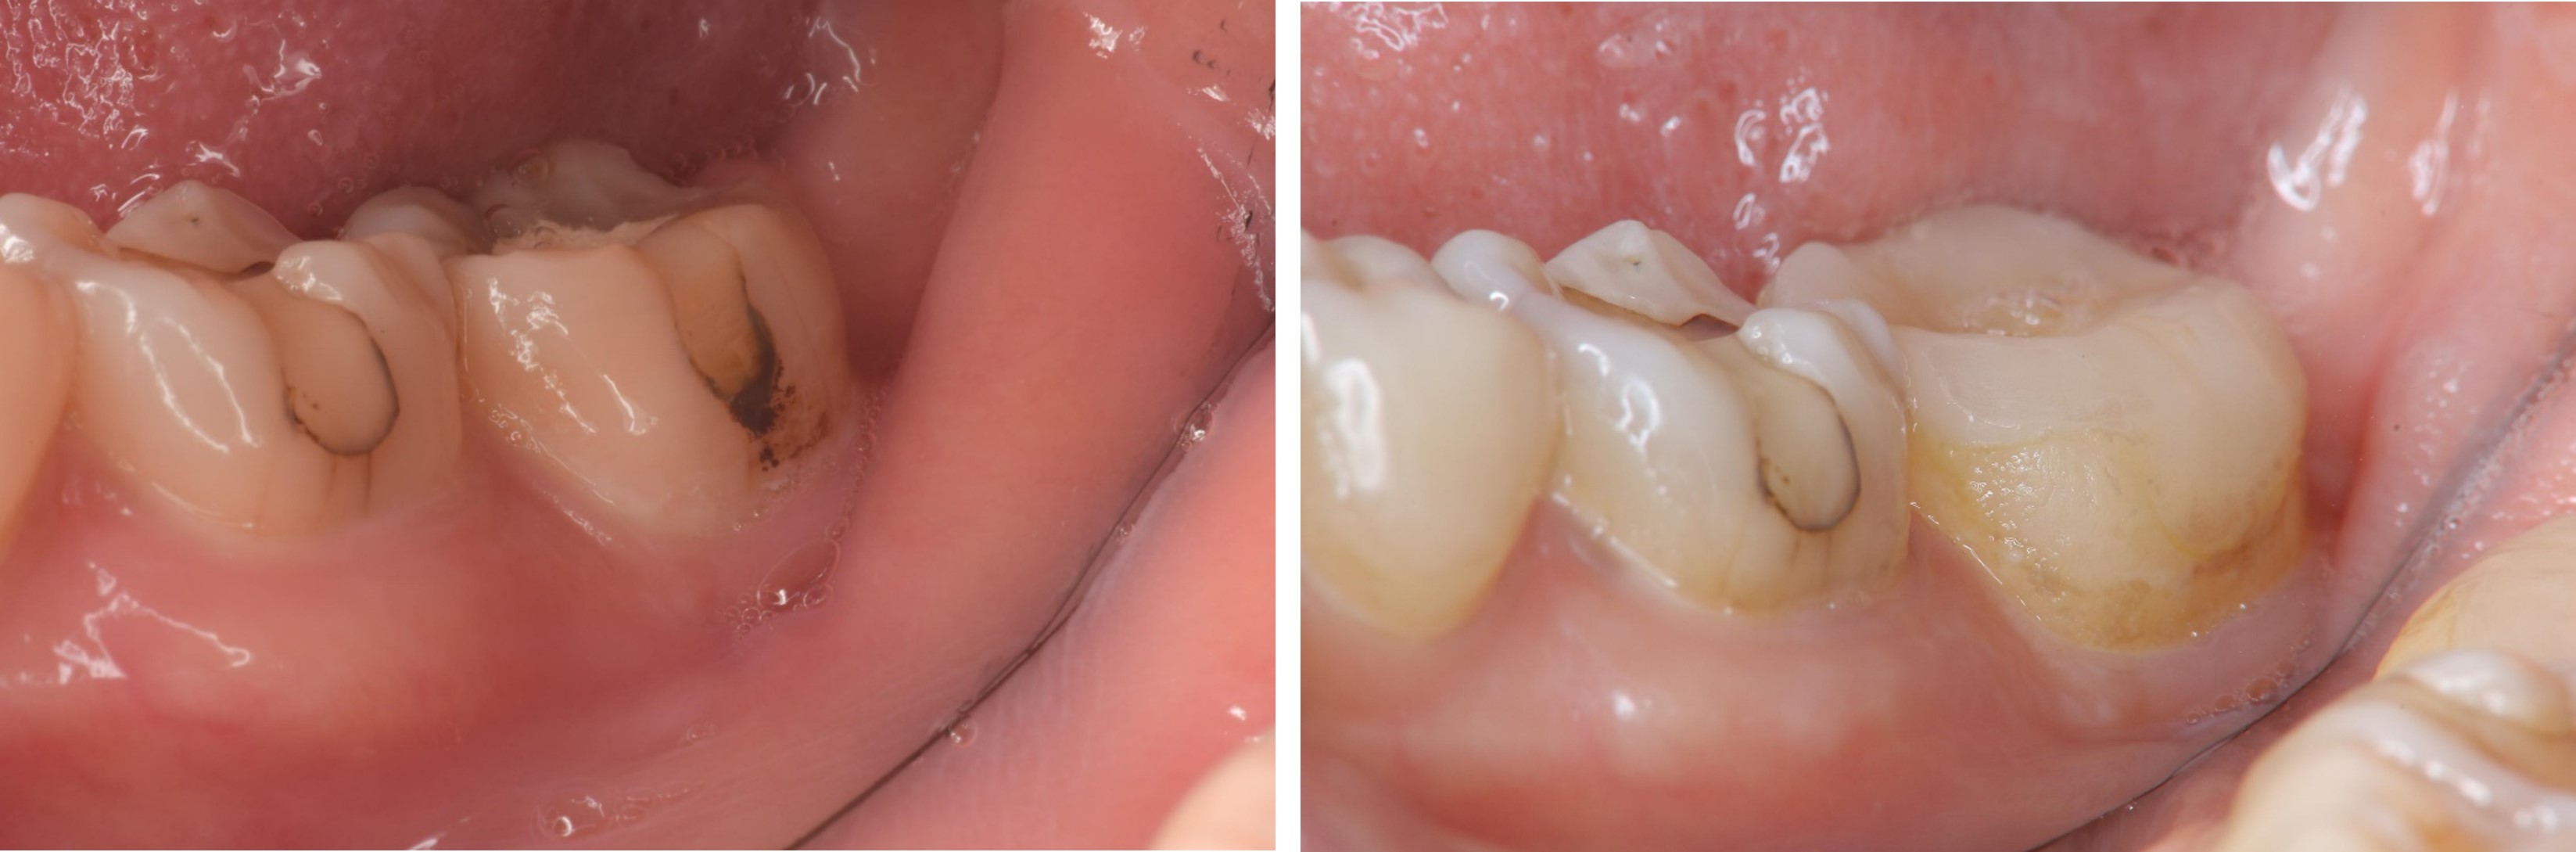

治療前,牙齒蛀牙至牙髓

術前、術後比較